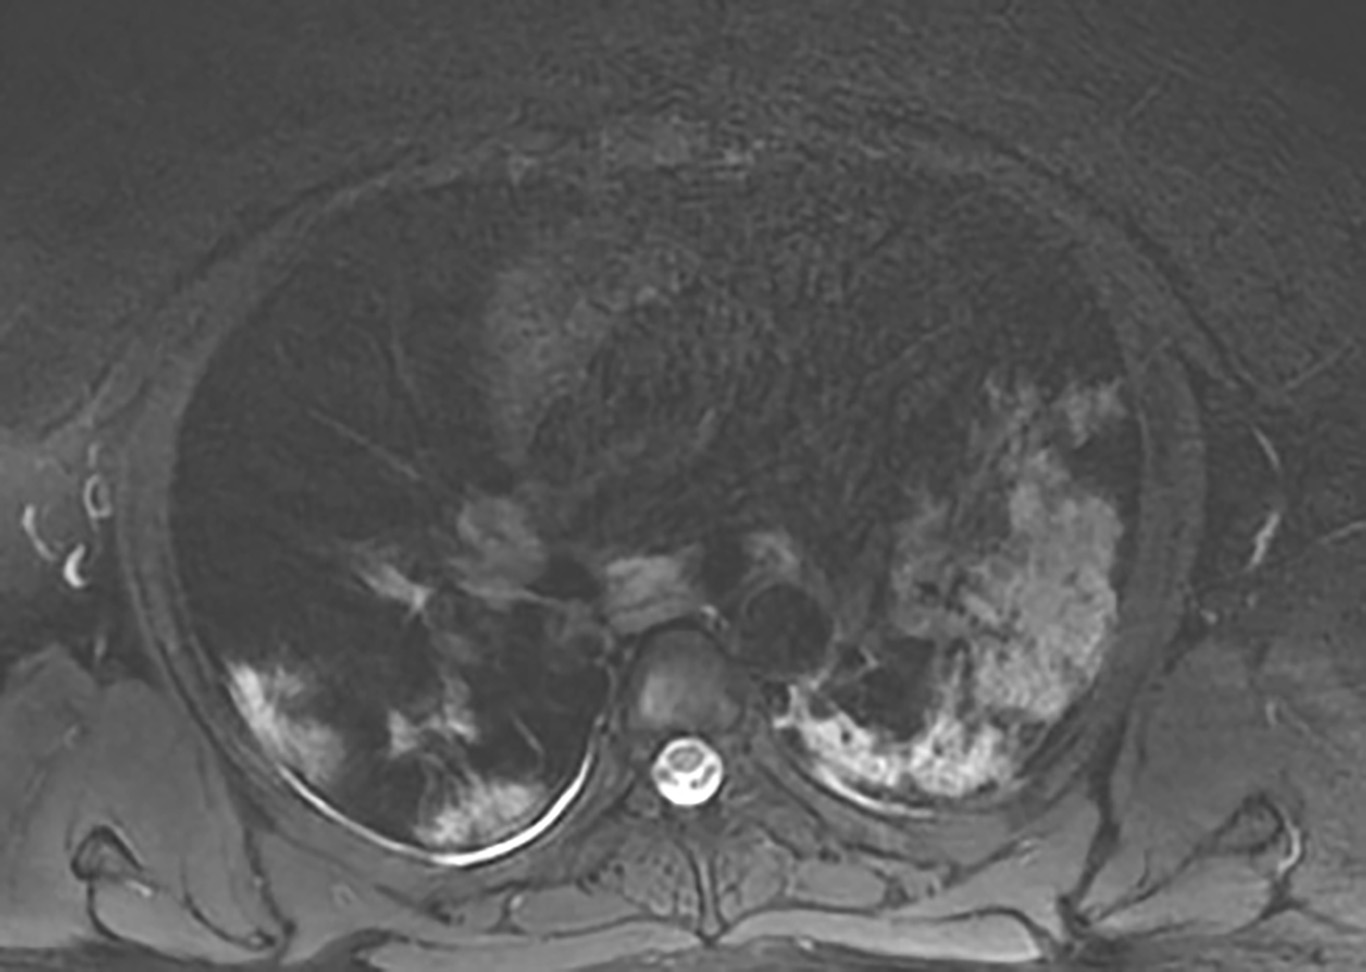

Рис. 2. Пациент, 28 лет, по данным КТВР в левом легком выявляются обширные зоны консолидации сливного характера, на фоне которых видны воздушные полоски бронхов (положительная бронхограмма). Меньшие по размерам зоны уплотнения легочной ткани визуализируются в кортикальном слое правого легкого (А); на Т2-ВИ, выполненных с применением импульсного режима PROPELLER FS, зонам консолидации соответствуют гиперинтенсивные участки, полностью совпадающие по размерам и локализации с данными, полученными при КТВР (Б); на Т1-ВИ зоны поражения отображаются участками средней интенсивности сигнала, несколько меньшего размера по сравнению с КТВР и Т2-ВИ

Рис. 5. Пациент, 56 лет, тяжелое течение COVID 19. При КТВР констатировано наличие множественных среднего размера зон консолидации в различных сегментах легких, преимущественно перибронховаскулярной и субплевральной локализации (А). При МРТ в нижней доле правого легкого наряду с гиперинтенсивными зонами по Т2 (В, стрелка) выявлялись разнокалиберные очаги повышенного сигнала на Т1-ВИ (Б, стрелки). Обнаруженные изменения расценены как альвеолярные геморрагии